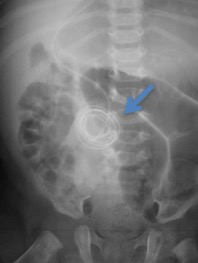

1 incision incorrecte, risque de suppuration cutanée (A) ; 2 incision correcte ; 3 fermeture sous-cutanée incorrecte ; fil à résorption lente, noeud non inversé, risque de saillie à travers la peau (B : flèche) ; fermeture correcte : sous-peau au fil à résorption rapide, points inversés idéalement une chirurgie en début de programme

- fermeture cutanée méticuleuse afin d’éviter absolument l’exposition de la tranche de peau et des fils sous-cutanés